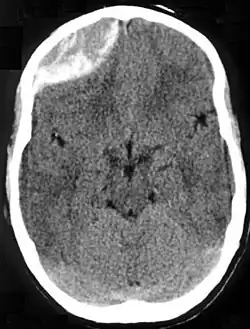

Nontraumatic epidural hematoma in a young woman. The grey area in the top right is organizing hematoma, causing midline shift and compression of the ventricle. Nontraumatic epidural hematoma in a young woman. The grey area in the top right is organizing hematoma, causing midline shift and compression of the ventricle.